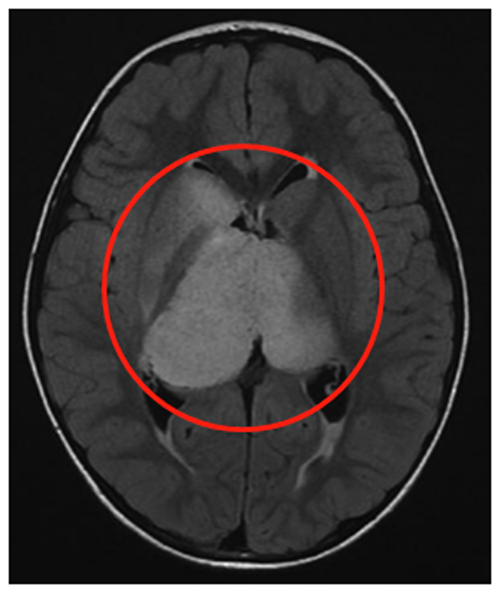

患者是一名6岁男童,症状为头痛、间歇性左上肢震颤。MRI(FLAIR序列)显示一个两侧丘脑肿瘤,右比左大,尾状核的右头部也参与其中。脑室轻度增大,膈膜水肿,肿瘤内部囊肿。因此,Rutka教授为其先行左额部内窥镜活检和鼻中隔造瘘术,再行左枕脑室-腹腔分流术。

(图8)